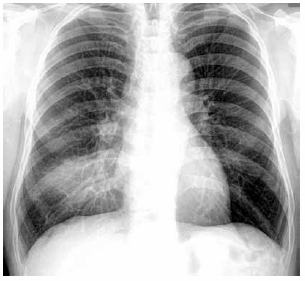

Homem de 51 anos de idade, em tratamento quimioterápico para câncer de cólon, apresenta quadro de mal-estar, sudorese, dispneia e tosse seca há 3 dias. O último ciclo da quimioterapia foi realizado há 10 dias. PA: 91 x 44 mmHg, FC: 114 bpm, FR: 28 ipm, SatO2: 89% e T: 38,3 ºC; tórax e abdome: NDN. Leucograma: 195/mm3. A radiografia de tórax realizada é apresentada a seguir.

Nesse momento, o melhor esquema antimicrobiano inicial é